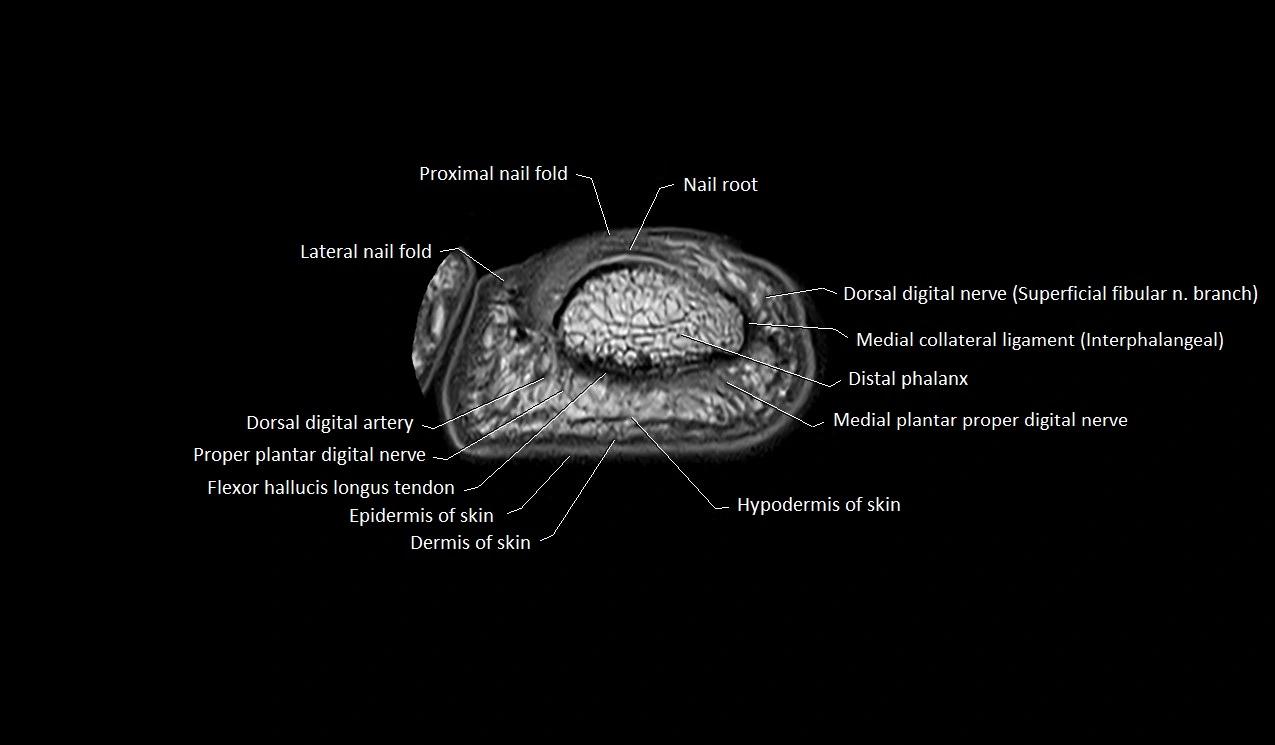

MRI image

image